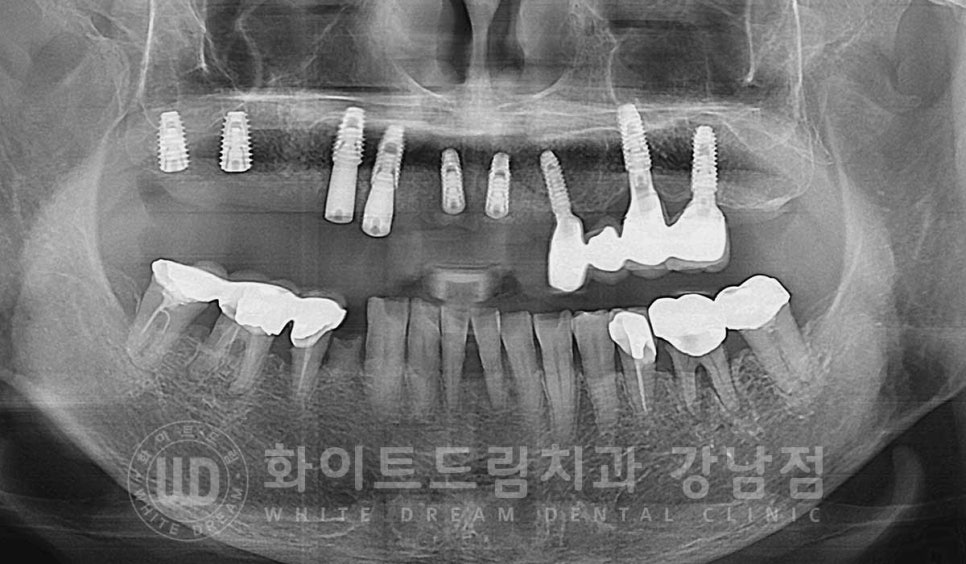

환자분의 당일 수술 후 x-ray 사진입니다.

상악 전체 임플란트 식립 후 / 수술 일자 : 23.08.10

식립된 임플란트를 보면 임플란트의 길이가 제각각인 것처럼 보이실 수 있습니다.

어떤 임플란트는 1차 수술만 진행하고, 어떤 임플란트는 2차 수술까지

진행했기 때문인데요.

자세히 보겠습니다.